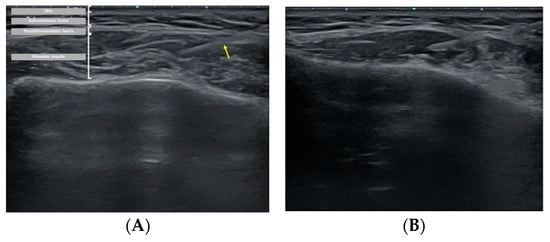

Figure 4. Ultrasound image showing injection dynamics after BoNT-A injection. (A) The yellow arrow notes the BoNT-A injection needle. Puncture was performed using a 1-cc syringe, with injection into the thickest region of the masseter muscle. (B) Immediate post-injection view.

The patient, who had previously received Botox injections in one masseter muscle using the landmark-guided, three-point injection technique, underwent injections on the opposite side of the face using the US-guided, single-point injection approach. Following the previously described method for masseter muscle assessment, the thickest region was identified using US B-mode, and its thickness (mm) was measured (Figure 2). Subsequently, with the US probe fixed in place, the injection needle was carefully guided into the muscle, ensuring proper and effective administration of the injection (Figure 3). Once it was confirmed that the injection was appropriately delivered at the thickest part of the muscle, the needle angle was adjusted to approximately 30 degrees in a thread-like manner to ensure even distribution of the drug throughout the remaining muscle parts (Figure 4). The needle was then withdrawn. The injection dosage remained consistent with the side that underwent landmark-guided, three-point injection.